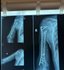

у ЗСУ назвали відсоток важких поранень ніг та рук | Фото: Рівненська обласна клінічна лікарня імені Юрія Семенюка

Для протезування кістки лікарі почали використовувати індивідуальні титанові імпланти, виготовлені за допомогою 3D-технологій. Завдяки цьому вдається при надскладних пораненнях врятувати кінцівки.

У повідомленні пригадали, як до лікарні привезли морського піхотинця із важким пораненням плеча. У нього не було частини кістки, вирвана велику ділянку м’язів, але збережений суглоб. Бійцю пощастило, оскільки на попередніх етапах лікування фахівці не ампутували руку. Раніше лікарі зі спини перемістили м’язи зі шкірою на плече. Згодом хірургам вдалося встановили імплант. Після операції воїн через три місяці вже міг непогано рухати рукою, що підтвердило ефективність застосування такої методики.

Процес виготовлення індивідуального титанового імпланта фахівці називають тривалим та доволі копітким. Спочатку хірург відправляє технічне завдання інженерам-волонтерам компанії Materialise. Вони створюють 3D-модель, а згодом — макет. Далі медик вносить свої зауваження, враховуючи конкретну ситуацію пацієнта. Згодом друкується імплант із титану, адже саме цей метал найкраще інсталюється в кістку.